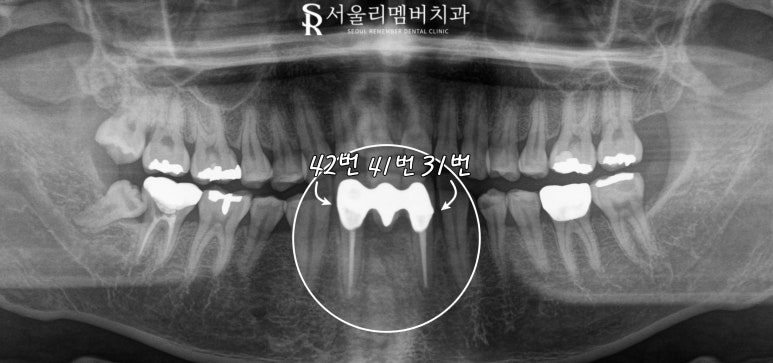

아래 앞니 3개가 보철로 씌워진 상황이며,

31번(하악 좌측 중절치)과

42번(하악 우측 측절치)을 지대치로 하여

제작된 브릿지는

기능적으로는 문제가 없었지만

심미성이 떨어지고 있었는데요,